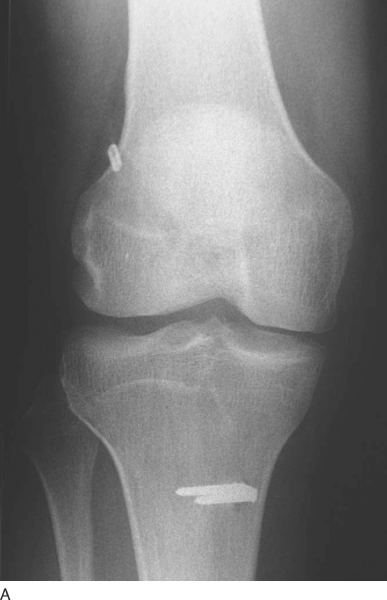

The patient is seen at 7 to 10 days for suture removal and postoperative radiographs (

Fig. 62-20

).